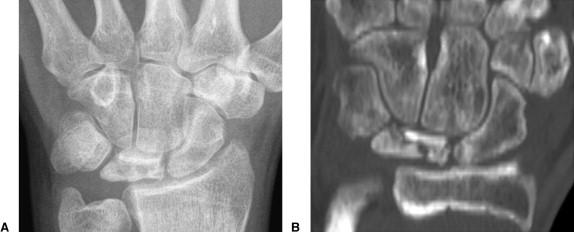

Stage III 부터는 주상골도 영향을 받기 시작하며 회전을 하거나(IIIA, cortical ring 관찰가능), carpal height 가 줄어드는 것을 확인할 수 있습니다. (IIIB), IIIA 까지는 II와 치료를 거의 동일하게 하지만, IIIB 부터는 Proximal row carpectomy 나 STT, SC fusion 등을 시행해 볼 수 있습니다.

단계별로 보면 다음과 같습니다.